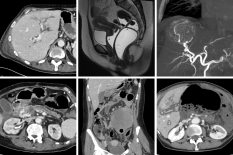

Module 1: Liver and biliary tract

Module coordinators : Prof. Christophe Aubé and Prof. Anita Paisant

Module 2: Pancreas

Module coordinator : Prof. Mathilde Wagner

Module 4: Emergency and Trauma

Module coordinator : Prof. Ingrid Millet

Module 5: Digestive Tract

Module coordinator : Prof. Céline Savoye-Collet

Module 6: Interventional Radiology

Module coordinator : Prof. Jean-Pierre Tasu